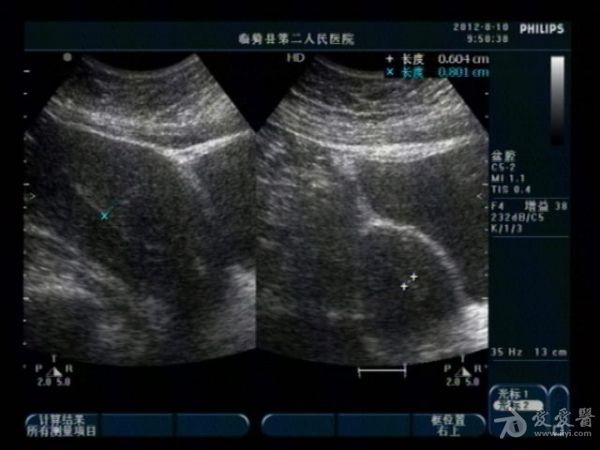

典型双子宫图像

前几天,我们科来了一位老病号,一年前剖腹产患者。当时手术证实“双子宫”今天超声图像可见一大一小两个子宫,右侧较大拟诊“子宫内膜异位症”。患者有经期腹痛史。

患者今年29岁,现生有一孩,就是剖宫产那个孩子。具体是那个子宫患者也不清楚,因在外地做的手术我们未能得到准确资料。患者近几个月来有明显的痛经史